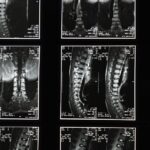

Tout d’abord, il est important de reconnaître que les douleurs cervicales peuvent être classées en deux catégories principales : aigües et chroniques. Les cervicalgies aigües sont souvent causées par un faux mouvement, un torticolis ou un traumatisme léger, tandis que les douleurs chroniques se manifestent sur une période prolongée, de plusieurs semaines à plusieurs mois. Cette distinction est cruciale pour choisir le traitement adéquat à mettre en place. Les douleurs dans la région cervicale peuvent également se manifester par des symptômes comme des raideurs, des maux de tête, des douleurs irradiant vers les épaules ou les bras, et même des vertiges.

Il existe plusieurs causes potentiellement responsables de l’apparition des douleurs cervicales. Les mauvaises postures au travail, particulièrement celles associées à un travail prolongé devant un écran d’ordinateur ou à l’utilisation accrue de smartphones, sont souvent en tête de liste. Les habitudes de sommeil inadaptées, si l’on ne dispose pas d’un soutien cervical suffisant, peuvent également exacerber ces douleurs. D’autre part, le stress qui engendre une tension musculaire dans la région du cou et des épaules joue aussi un rôle significatif. Le vieillissement naturel et des pathologies comme l’arthrose ou les hernies discales contribuent également à la gravité des cervicalgies avec le temps.